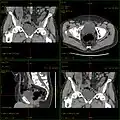

Für die Darstellung des Knochens oder eines Nierensteins ist kein Kontrastmittel nötig. Wenn die Beurteilbarkeit des Weichteilgewebes nicht gewünscht wird, wird daher auch kein Kontrastmittel injiziert. Im Gegensatz dazu wird für Fragestellungen, die den Brust- und/oder Bauchraum betreffen, fast immer Kontrastmittel verwendet (so eine KM-Allergie oder Niereninsuffizienz dies nicht verbieten). Je nach Fragestellung wird eine Region ein- oder mehrfach gescannt. Folgende Aufnahmetypen werden typischerweise benutzt:

• Nativ-Aufnahme ohne Kontrastmittelgabe

• Arterielle Aufnahme, die die gefüllten Arterien zeigt, nicht jedoch die Venen; für die Beurteilung des Gewebes ist sie wenig geeignet und wird ca. 20 bis 30 Sekunden nach Kontrastmittelgabe gestartet.

• Venöse Aufnahme, die Venen sowie Gewebe in gutem Kontrast zeigt und ca. 60 bis 70 Sekunden nach Kontrastmittelgabe erfolgt.

• Bisweilen auch: Spätaufnahmen (LVCT = late venous CT), die 90 Sekunden bis wenige Minuten nach Kontrastmittelgabe erfolgen.